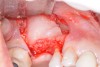

Growth-factor hydrated freeze-dried bone allograft.

Figure 14